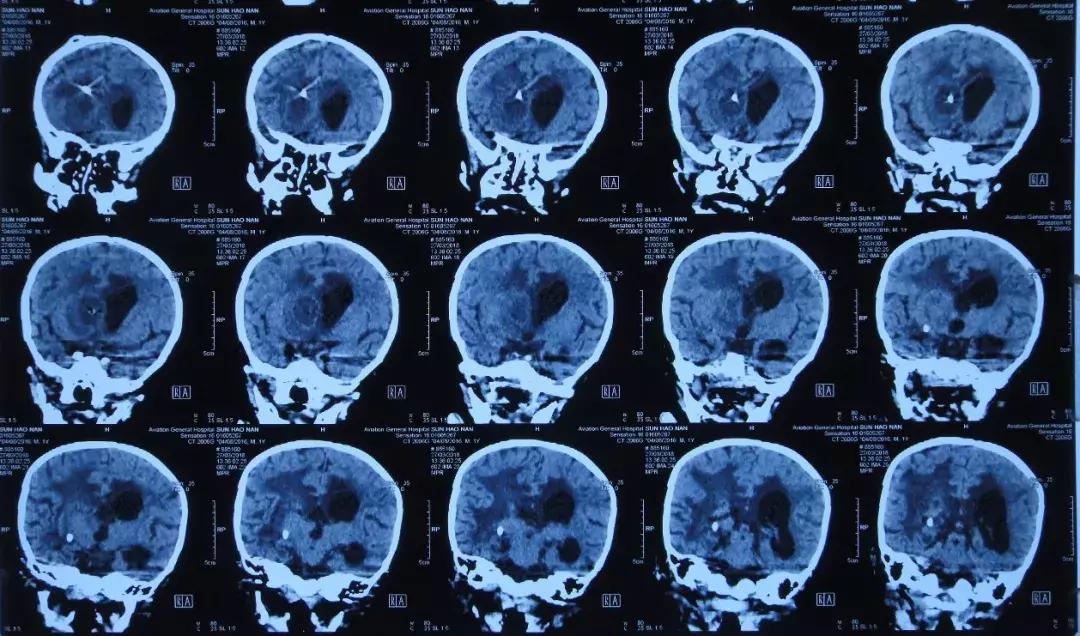

2018年5月17日头部影像检查

李小勇主任指导意见:患者诊断“脑积水”明确。根据目前情况,患者脑脊液性质可,脑脊液细菌培养阴性,无发热及呕吐症状,2018年5月17日行脑室腹腔分流腹腔端置入术。

2018年5月31日头部影像检查

2018年8月19日复查头部影像